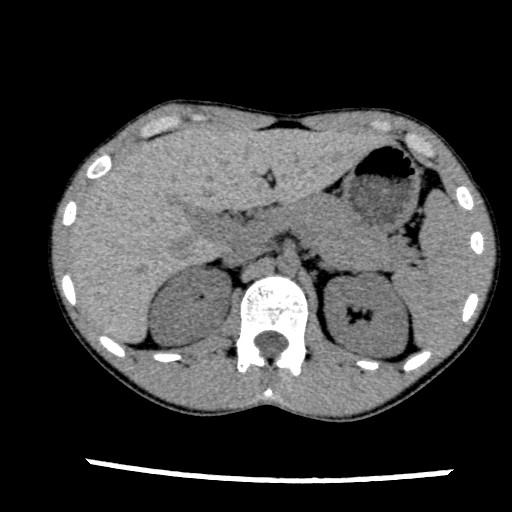

頭部と腹部の画像です。

CTの基本的な画像で、体を輪切りにしたものです。